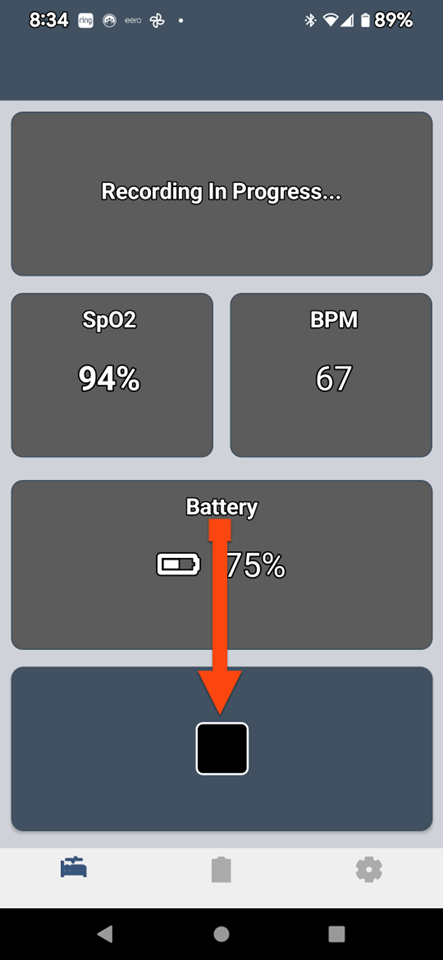

SLEEPIMAGE APP (Android)

SLEEPIMAGE APP (Android)

SLEEPIMAGE APP (Android)

SLEEPIMAGE APP (Android)

SLEEPIMAGE APP (Android)

SLEEPIMAGE APP (Android)

SLEEPIMAGE APP (Android)

SLEEPIMAGE APP (Android)

SLEEPIMAGE APP (Android)

SLEEPIMAGE APP (Android)

SLEEPIMAGE APP (Android)

SLEEPIMAGE APP (Android)

SLEEPIMAGE APP (Android)

SLEEPIMAGE APP (Android)

SLEEPIMAGE APP (Android)

SLEEPIMAGE APP (Android)

SLEEPIMAGE APP (Android)

SLEEPIMAGE APP (Android)

SLEEPIMAGE APP (Android)

SLEEPIMAGE APP (Android)